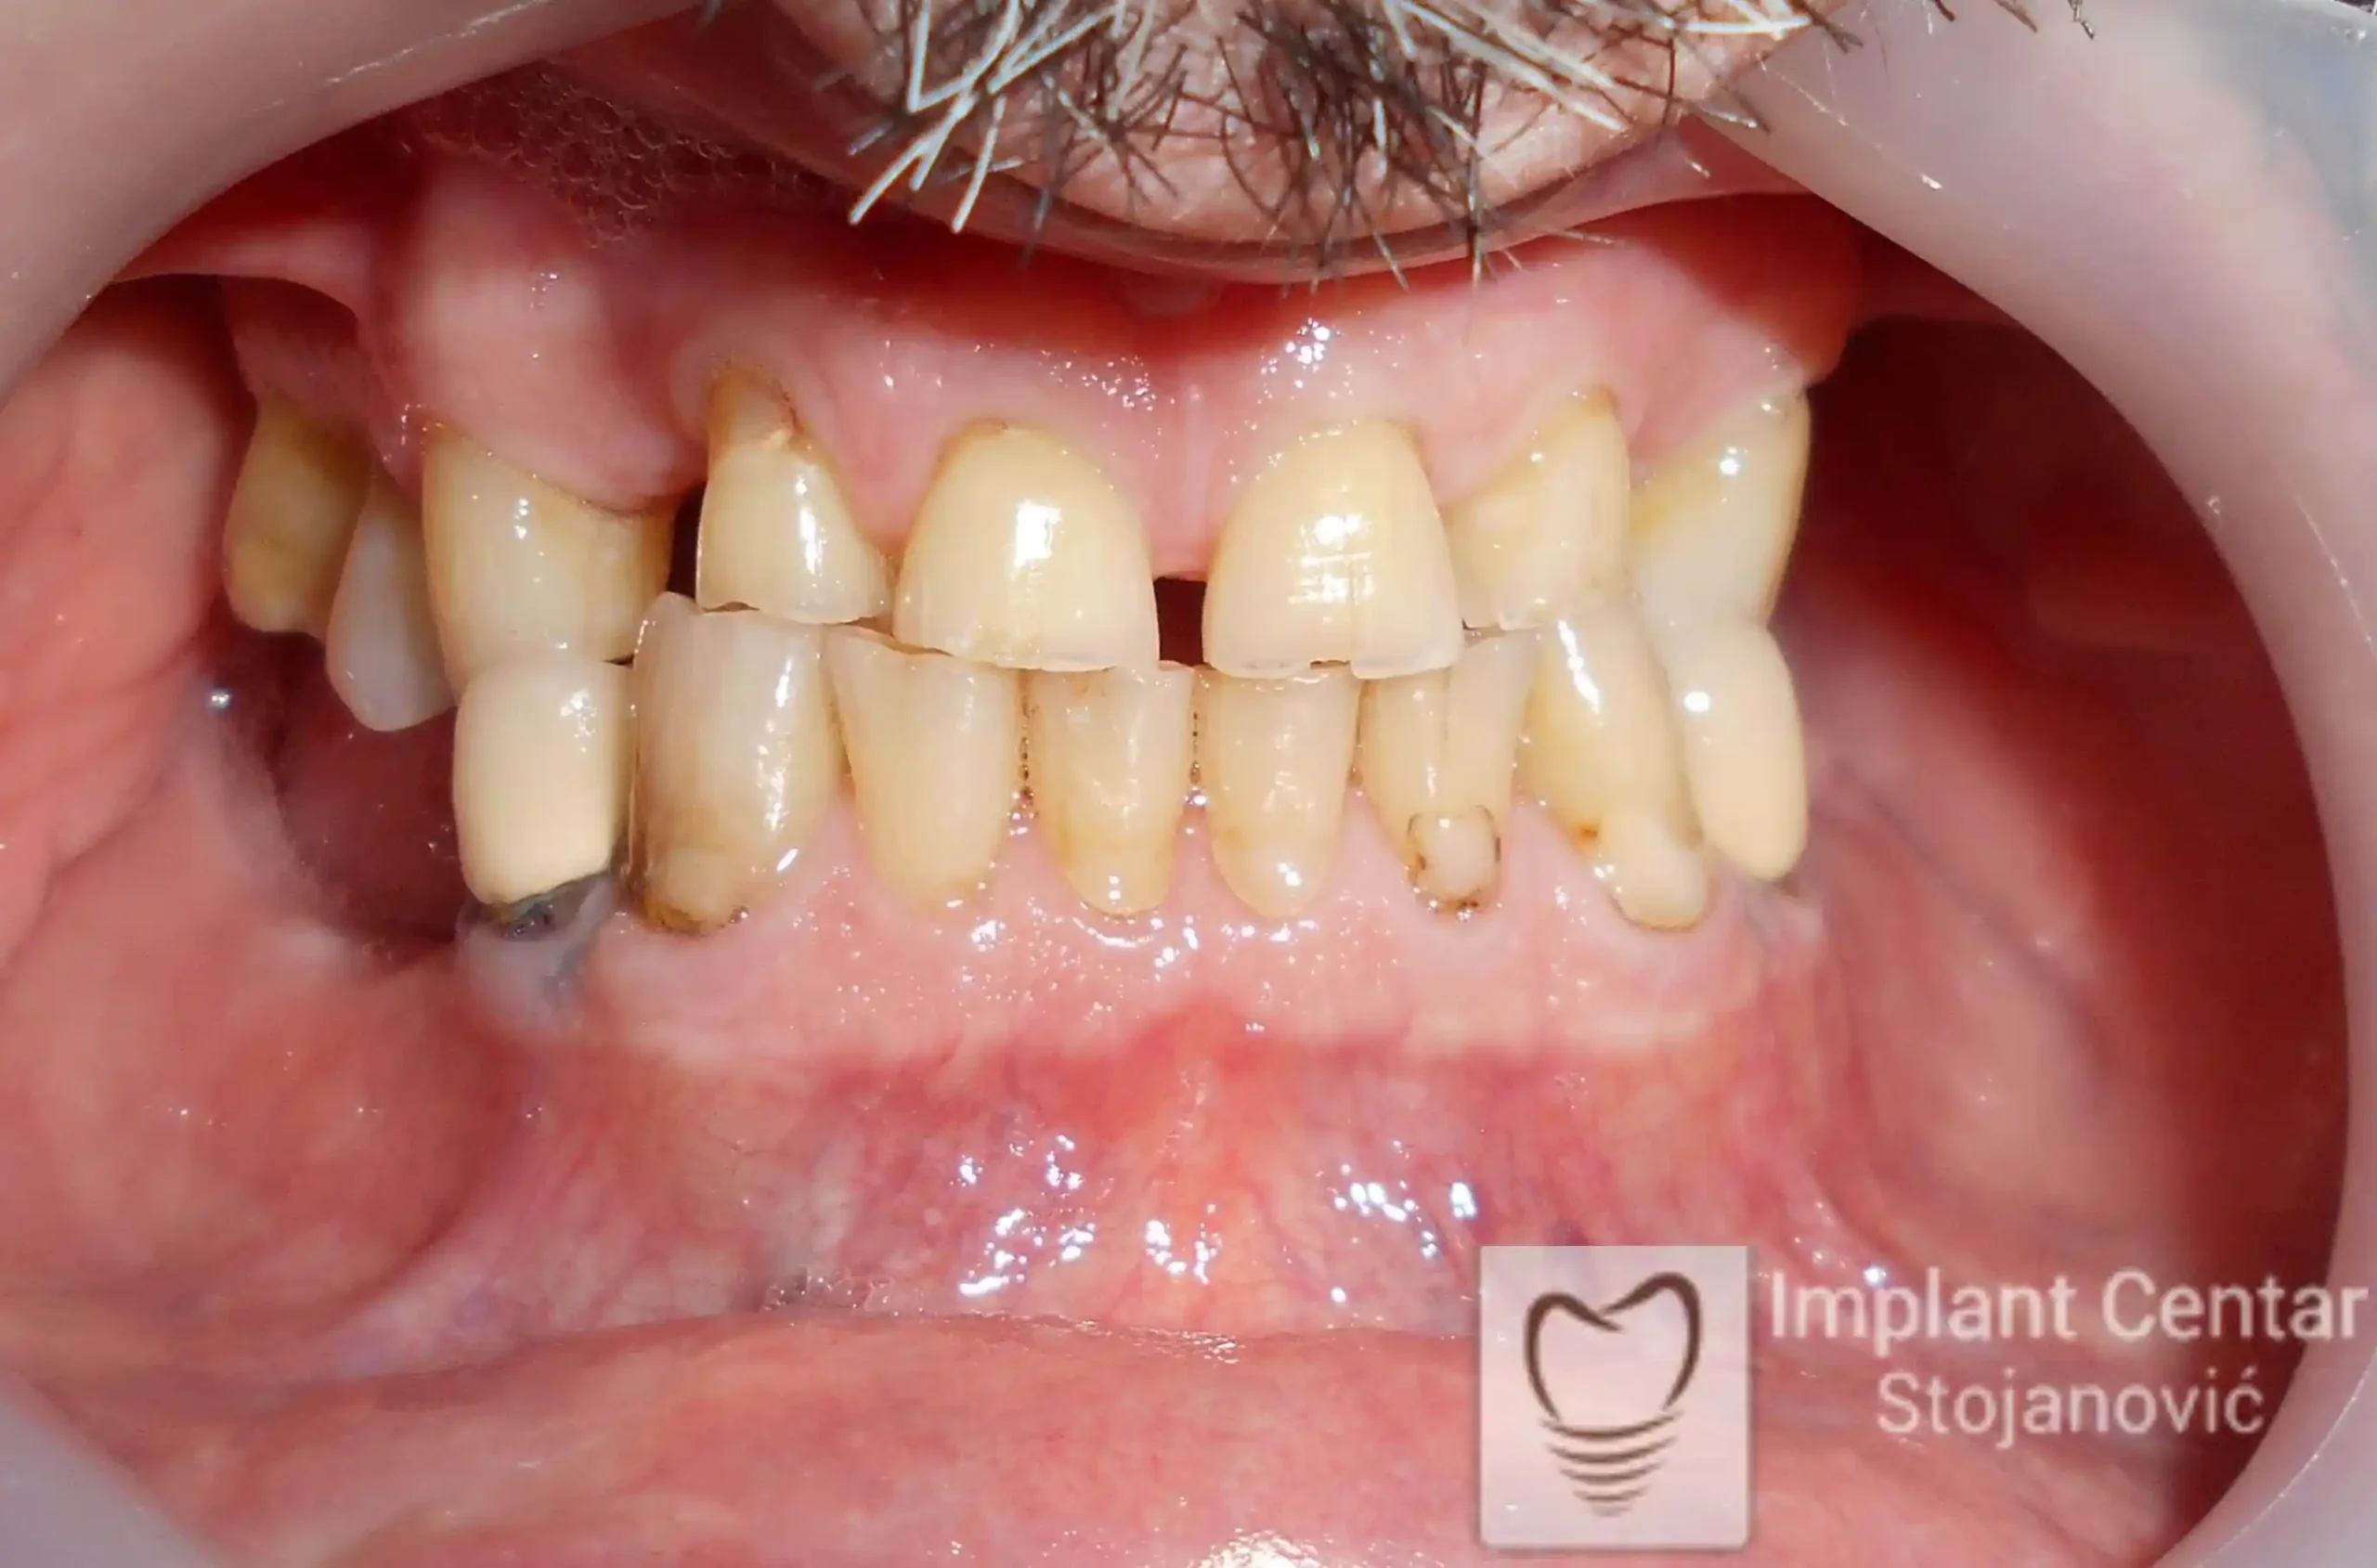

Pacijent sa rascepom usne, nepca i alveolarnog grebena uspešno je rehabilitovan fiksnim protetskim radom na implantatima. Pre dolaska u našu ordinaciju, pacijent je u gornjoj vilici nosio totalnu protezu preko preostalih zuba, dok je u donjoj vilici bio zbrinut parcijalnom mobilnom protezom. Tokom višegodišnje potrage za adekvatnim rešenjem, pacijent nije uspeo da pronađe zadovoljavajuću terapijsku opciju ni u zemlji ni u inostranstvu.

Nakon detaljnog kliničkog pregleda i analize radioloških snimaka, izrađen je sveobuhvatan plan terapije sa ciljem uklanjanja mobilnih proteza i postizanja maksimalne funkcionalne i estetske rehabilitacije. Zbog loše biološke vrednosti preostalih zuba, doneta je odluka o njihovom vađenju i ugradnji dentalnih implantata.

Poseban terapijski izazov predstavljalo je premošćavanje defekta nastalog usled rascepa, kao i ograničena količina raspoložive kosti u gornjoj vilici. Primenom većeg broja implantata i odgovarajućih procedura nadoknade kosti, postignuta je stabilna osnova za fiksni protetski rad.